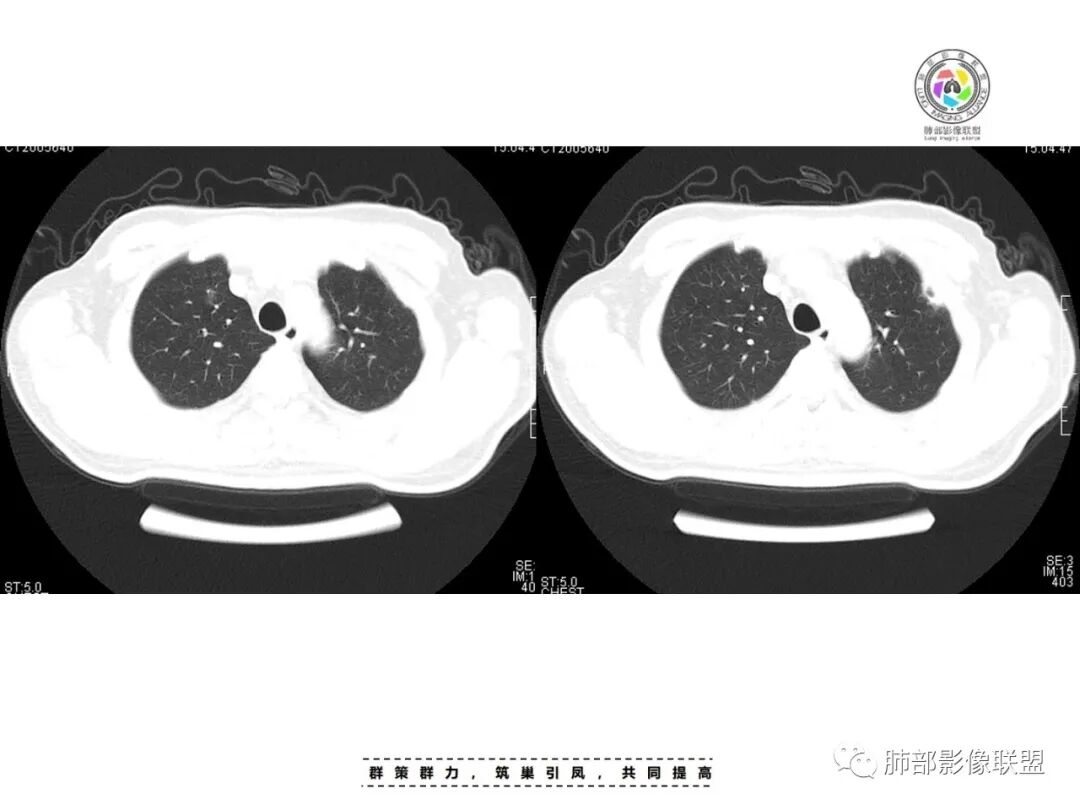

李:双肺多发结节,部分空洞,胸膜下为主,考虑血源性,治疗后好转,如果抗炎好转,考虑化脓菌栓,肺克或金葡,如激素治疗后考虑gpa亚东:双肺多发结节,部分见空洞,与血管关系紧密,考虑感染性病变,短期内变化快,糖尿病史,金葡,肺克?王秀仙:糖尿病基础上伴发的多发结节,部分空洞,四大金刚金毛结克,首选肺克琦遇:糖尿病四大金刚里按病史只有金葡和肺克符合,病灶特点,胸膜下为主,病灶偏少,有不干净空洞,肝功无异常,金葡可能性大!大雄:但是没有发热 小强:糖尿病史,胸膜下,6天空洞增大,金葡可能,肺克一般进展后有融合大片改变,这个没有,但是金葡临床症状更重,这个也看不出来崔少钢:中年男性,血糖控制不良,感染指标高。影像:双肺多发的结节、空洞,分布比较随机,考虑肺克。病变变化不够快,囊张力不够高,感觉不像金葡。大雄:血流感染的金葡 与肺克影像上有重叠,不一定好区分肺克炎性指标(PCT)可以高的更明显金葡血流感染一般有可追寻的来源,比如皮损,软组织脓肿,骨髓炎,心内膜炎等肺克一般是来源肠道,经门脉系统入肝,形成肉眼可见的肝脓肿或者不可见的隐匿性微脓肿,再经肝静脉回流→下腔静脉→右心→肺动脉→肺内播散张小兵:糖尿病基础,胸膜下多发结节伴空洞形成,这么大的空洞结节无播散,排除结核。肉芽肿性多血管炎,一般累及支气管,引起支气管狭窄,也可排除,倾向肺克,鉴别金葡。流心明智:男性,51岁,以咳嗽、咳痰、气喘3天。既往糖尿病10年。血常规wBC及中性比、CRP、PCT均升高。CT示:双肺多发结节、小斑片影,胸膜下多,大部分实性、部分伴空洞,大部分类圆形、部分呈楔形,部分病灶可见滋养血管征,治疗后逐渐吸收。考虑:感染性病变,SPE,金葡>肺克,鉴别隐球、TB等。

一、双肺多发结节或小片影,随机分布,而未见支气管壁增厚及支气管远端如树芽征等改变,提示病灶来源于血道;且肺内结节边缘模糊,常可排除转移(一般转移瘤边缘多较光整,患者常有恶性肿瘤病史,且呼吸道症状不明显或出现较迟);

影像表现:双侧结节,常伴空洞形成,最多见于肺外周和肺下野,结节的边界清晰或模糊;可伴有斑片状实变区;多表现为基底贴近胸膜的楔形实变影,其内密度均匀或不均匀,可形成空洞。